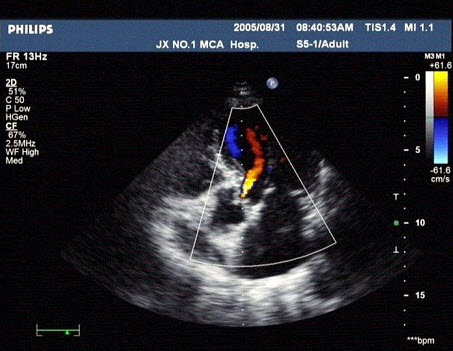

某患者收缩期超声心动图所示,提示()

A.二尖瓣狭窄

B.二尖瓣关闭不全

C.房间隔缺损

D.动脉导管未闭

E.以上都不是